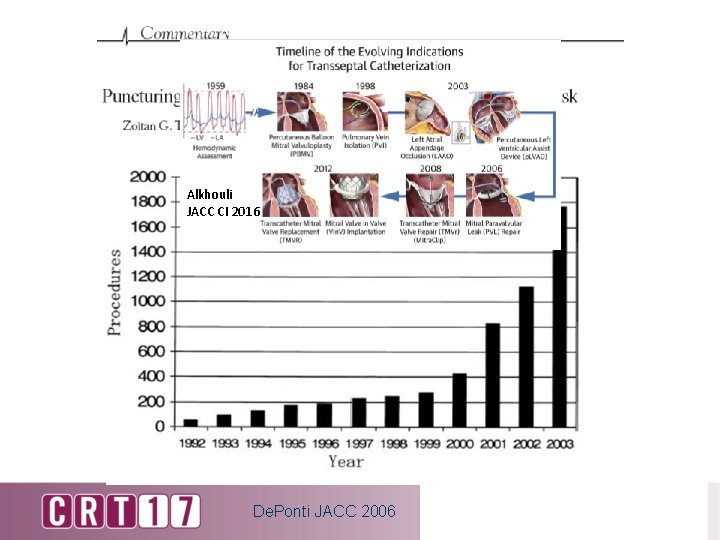

Alkhouli JACC CI 2016 De. Ponti JACC 2006